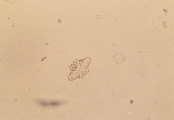

Кристаллы кальция оксалата дегидрата обычно бесцветные, характерной октоэдрической или овальной формы (рис. 4-11). Под световым микроскопом выглядят как большие или маленькие квадраты, углы которых соединены диагональными линиями. Кристаллы кальция оксалата обнаруживаются в кислой, нейтральной или щелочной моче.Кристаллы кальция оксалата моногидрата различаются по размерам и могут быть в форме веретена, овальными (как конопляное семечко) или в форме гантели (рис.12). Кристаллы кальция оксалата моногидрата были обнаружены у собак с закисленной мочой, особенно у животных с отравлениями этиленгликолем (рис. 13-17). Они растворимы в соляной кислоте, но не растворимы в уксусной кислоте. Кристаллы могут встречаться в комбинации с кальций оксалат дегидратами и другими типами кристаллов.

Рис. 4. Микрофотография кристаллов кальция оксалата дегидрата, обнаруженных в мочевом осадке 5-летней суки Бишон-Фриза (не окрашено, увеличение Х 250).